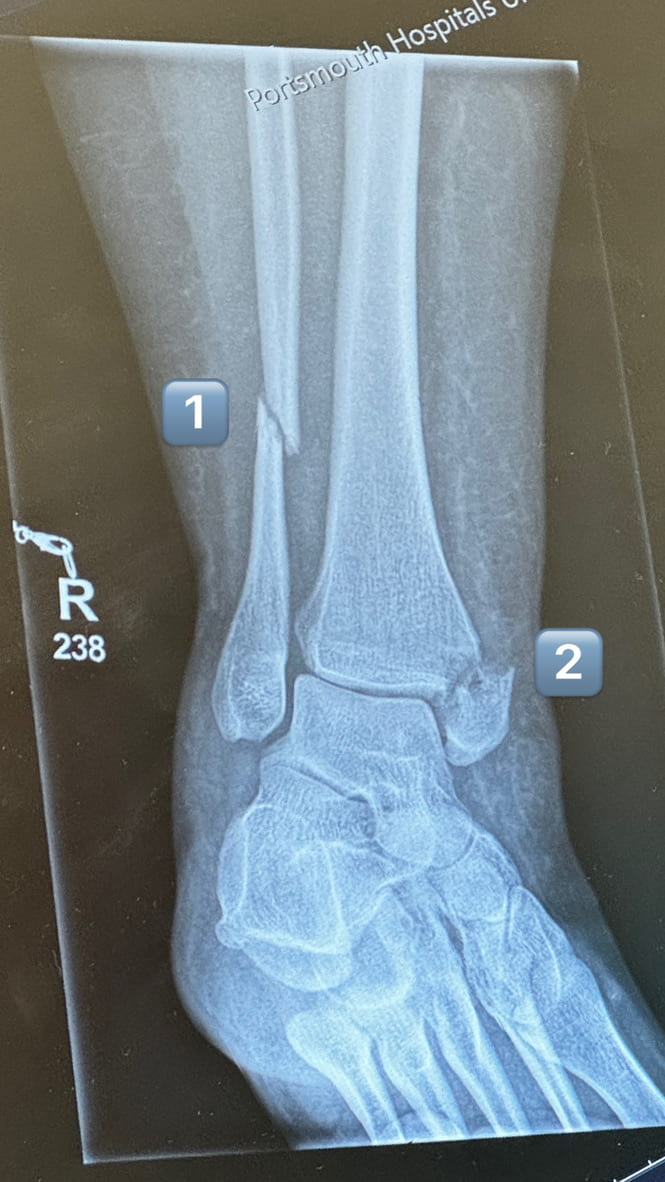

Above: my 3 breaks

Eventually, about 3am I think, the images came back - 3 breaks. They said I’d see a consultant who would decide it if just needed casting or of I would need surgery. ‘SURGERY!” I shouted (literally shouted) in surprise. The nurse looked at me and said something like “yes, you’ve done quite a job here!” (smiling I might add!).